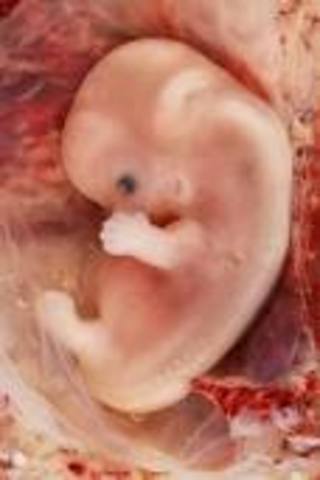

Month 2

Mom: Swelling of the breast, pressure of the bladder, and morning sickness.

Baby: About 1/4 inch long, facial parts take shape, bones are beginning to form.